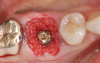

Recognizing that achieving primary stability in extraction sites is more challenging than in healed ones, the use of tapered implants may be considered to achieve better primary stability for immediate implant placement. Kan and colleagues reported decreased rotational instability with tapered implants in immediate placement protocols.9 Utilizing an implant with well-defined threads that improve lateral bone engagement may improve stability (Figure 1 through Figure 4). Conceptually, it makes sense to use tapered implants or those with threads that cut and condense bone; however, there is little evidence in the literature supporting superior primary stability based on implant design.10 Although implant design may offer advantages, clinicians should focus more on site preparation and final drill selection as the keys to achieving adequate primary stability.

(4.) This series of clinical images illustrates the use of an implant with well-defi ned

threads that improve lateral bone engagement. In a multirooted extraction socket where there are large voids, this can help to achieve initial implant stability.

Figure 4